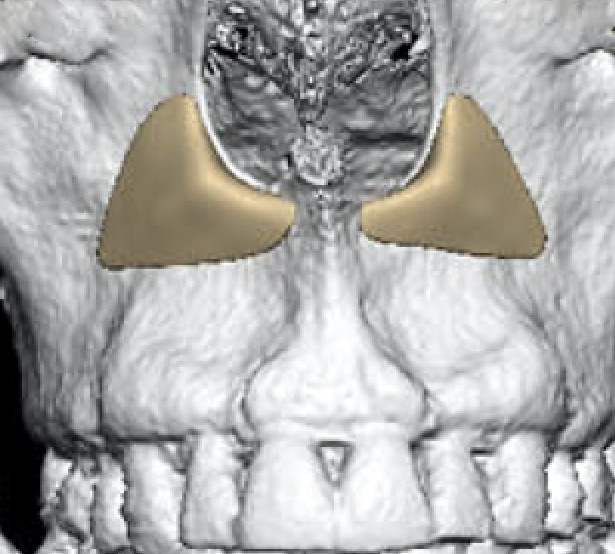

paranasals

as you can see now that some swellings gone down my nasolabials are getting more prominent again. I don't want fat grafting, i wanted to fake some bone support instead. Surgeon thinks a facelift oughtta do it, but id rather augment the structure, facelift seems like a subscription based service where ive gotta do it again and again over the years to keep fixing it.

I've seen a few different shapes, ones with a hood on each side of the nose, ones with one big hoof under the nose, and ones that trace all the way up the side if the nose and also augment the infras. This is more of a full midface augmentation. Do these look stupid in practice or no?

Should I get paranasals, and what shape would work best?

as you can see now that some swellings gone down my nasolabials are getting more prominent again. I don't want fat grafting, i wanted to fake some bone support instead. Surgeon thinks a facelift oughtta do it, but id rather augment the structure, facelift seems like a subscription based service where ive gotta do it again and again over the years to keep fixing it.

I've seen a few different shapes, ones with a hood on each side of the nose, ones with one big hoof under the nose, and ones that trace all the way up the side if the nose and also augment the infras. This is more of a full midface augmentation. Do these look stupid in practice or no?

Should I get paranasals, and what shape would work best?